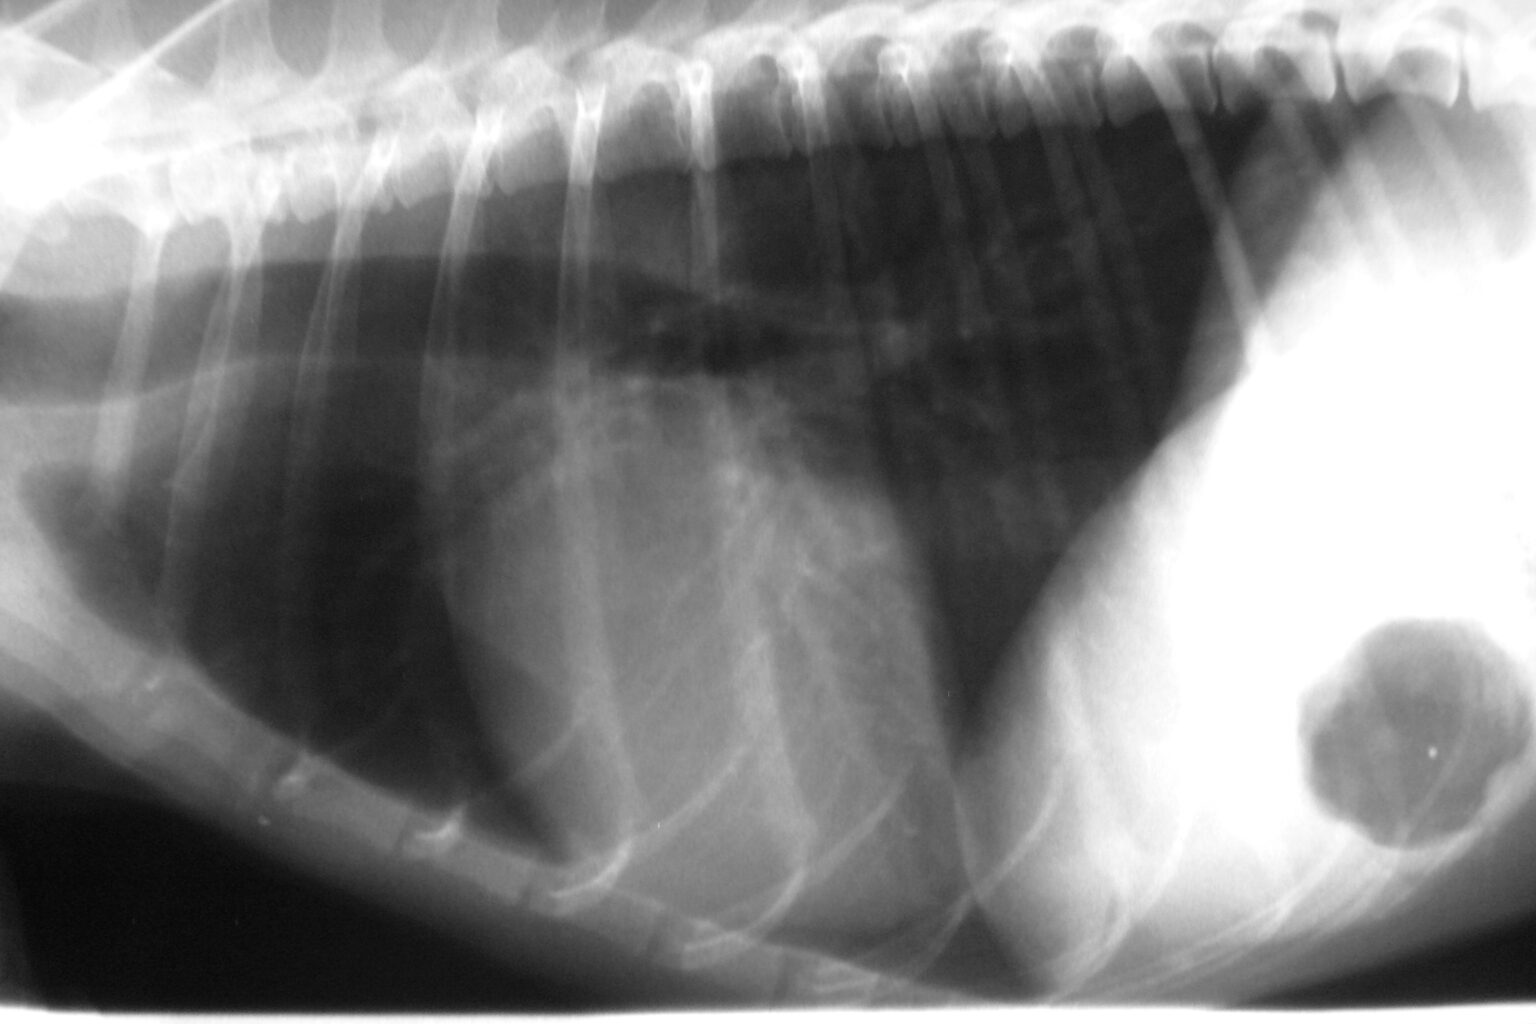

Im Gegensatz zu den Katzen bekommen ältere Hund relativ oft eine Herzinsuffizienz (Herzschwäche oder Herzvergrößerung), zum Teil mit Herzhusten und Wassereinlagerungen. Die Vergrößerung des Herzens kann zu einer Verringerung seiner Pumpleistung führen, was eine unzureichende Zirkulation von sauerstoffreichem Blut im Körper zur Folge haben kann.

Flüssigkeitsansammlung : Wenn das Herz nicht mehr effektiv arbeitet, kann sich Flüssigkeit in der Lunge ansammeln (Lungenödem), was ebenfalls zu Husten führt. Im Gegensatz zu den Katzen bekommen ältere Hund relativ oft eine Herzinsuffizienz (Herzschwäche oder Herzvergrößerung), zum Teil mit Herzhusten und Wassereinlagerungen. 5 mg/kg) sollte zunächst über 3 Tage beibehalten werden

Diaphragma hund dog Fotos und Bildmaterial in hoher Auflösung Alamy. Bei erwachsenen oder älteren Hunden sind die häufigsten Erkrankungen eine Herzmuskelschwäche (große Hunde) und eine Undichtigkeit der Herzklappen (kleine Hunde) Schnelle Ermüdung: Hunde mit Herzkrankheiten zeigen oft eine verminderte Ausdauer